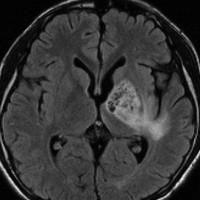

ICE化学療法投与開始から数日で小さくなります

この例は古いので第3脳室開窓術 ETV をしていません。左はICE化学療法前。中央は9日後。右は25日後です。閉塞性水頭症があっても1週間くらいで中脳水道が通って水頭症は改善します。ジャーミノーマであれば,ICE化学療法1コースでかなり縮小するはずです。このような顕著な効果がない時には,逆にジャーミノーマ以外の胚細胞腫瘍が混在していると考えた方がいいでしょう。多くは奇形腫の混在です。